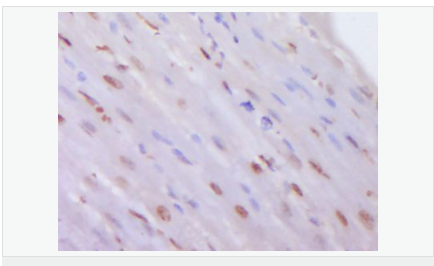

交叉反應:Human,Mouse,Rat(predicted:Pig,Cow,Rabbit,Fruit Fly) 推薦應用:WB,IHC-P,IHC-F,ICC,IF,Flow-Cyt,ELISA

| 產品應用 | WB=1:500-2000 ELISA=1:5000-10000 IHC-P=1:100-500 IHC-F=1:100-500 Flow-Cyt=0.2μg /Test ICC=1:100-500 IF=1:100-500 (石蠟切片需做抗原修復) not yet tested in other applications. optimal dilutions/concentrations should be determined by the end user. |